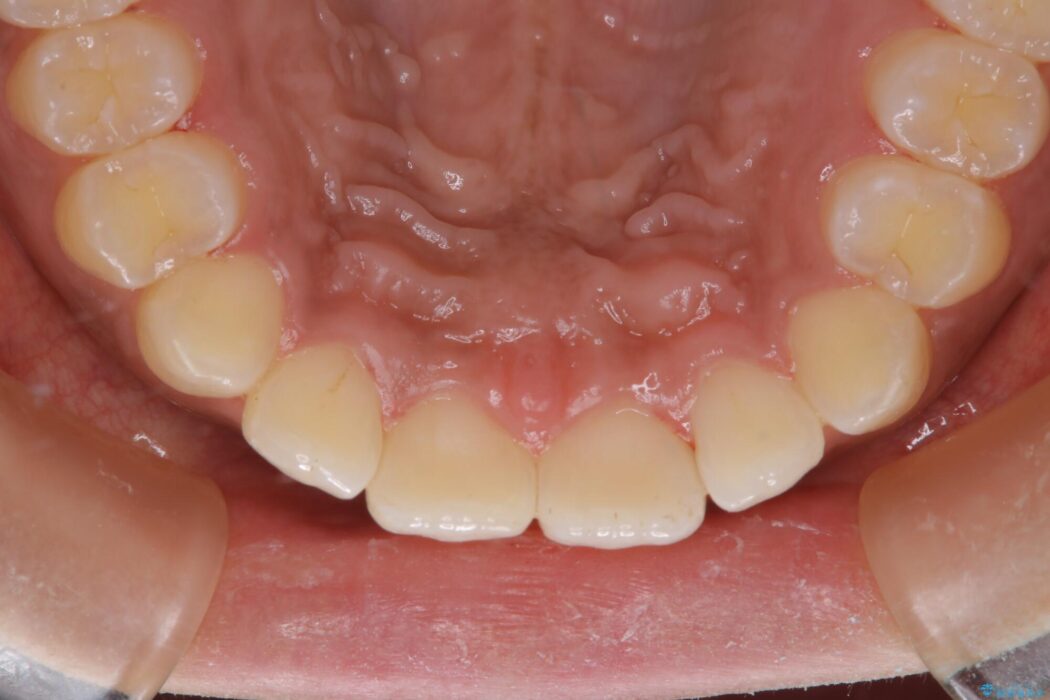

【20代女性】タバコのヤニ(ニコチン、タール)を徹底的に除去

タバコによって付着したステインを綺麗にしたいとのことで来院されました。

ステインがこびりついていたため、PMTC60分コースを行いました。

治療後について

タバコに含まれているタールが歯の黄ばみの原因になります。その黄ばみなどを、無理に落とそうとしたりすると歯の表面に傷がついてしまったり余計に汚れがつきやすい状態になることがあります。

PMTCでは、専門の機材を使用し、歯の表面の凸凹にミネラルを補給して、ツルツルの表面に仕上げます。定期的にPMTCを行うことにより、歯質の強化になり着色がつきにくい状態になります。